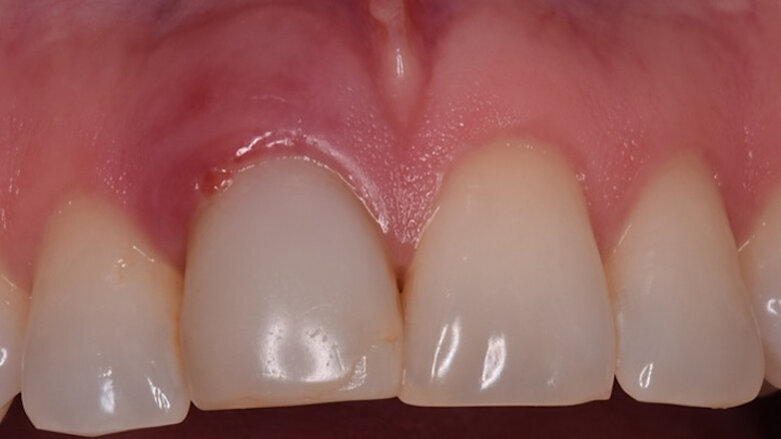

Figuras 21 y 22. Imágenes del día de la intervención y a los 2 años de evolución. Se observa una regeneración casi completa del periodonto, a pesar de presentar un defecto óseo inicial muy importante en la tabla ósea cortical vestibular. Con esta técnica solucionamos en un solo acto quirúrgico, tanto la preservación como la regeneración ósea, con gran estabilidad de los resultados en el tiempo.

Figuras 21 y 22. Imágenes del día de la intervención y a los 3 años de evolución. Se observa una regeneración casi completa del periodonto, a pesar de presentar un defecto óseo inicial muy importante en la tabla ósea cortical vestibular. Con esta técnica solucionamos en un solo acto quirúrgico, tanto la preservación como la regeneración ósea, con gran estabilidad de los resultados en el tiempo.